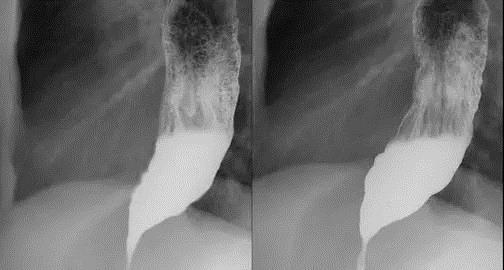

24岁男性患者,因“吞咽困难2年余”之主诉入院,2年前,患者出现吞咽困难症状,可进全流食,不能进固体食物;有饭后胸部胀痛,反流,呕吐症状,呕吐物为食物残渣;来我院内镜中心行胃镜检查示:食管下段扩张受限,可见食物潴留,中上段食管可见扩张。考虑贲门失迟缓。后患者行食管造影,表现为典型鸟嘴征,明确为贲门失弛缓症。遂来我院行POEM手术。

造影示:鸟嘴征